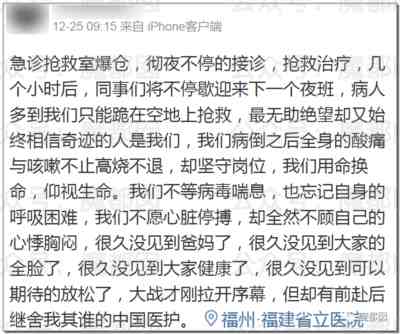

第六、现在医护真的有那么忙吗?是真的!

我们已经贴了不知道多少了,现在最苦最累的就是医护们,拼死拼活的抢救,所以请大家多给他们一点容忍和理解!